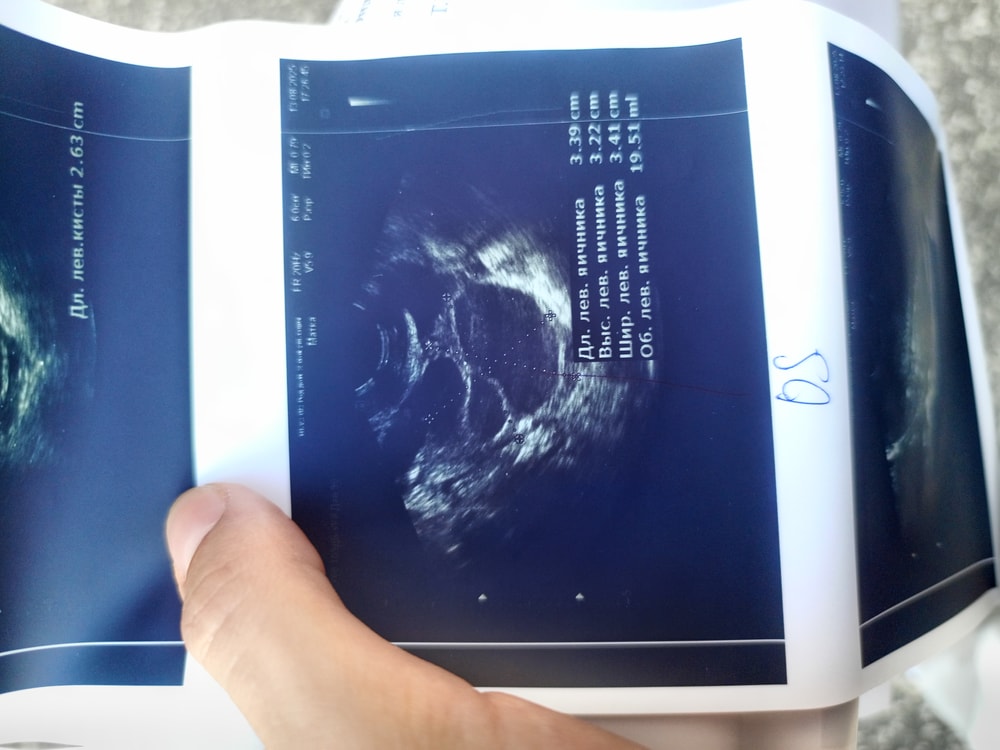

Приложу фото яичника, вчера писала пост о том, что уже даже у хирурга была из за боли, боль в яичнике при нажатии, при чихе, смехе, кашле, сегодня сходила к гинекологу, пока смотрела на кресле и параллельно давила на живот я аж заорала от боли, она сказала что боль от кисты жёлтого тела(26 мм) ..Но мне не верится, что от жт такая боль может быть.. Что скажете?